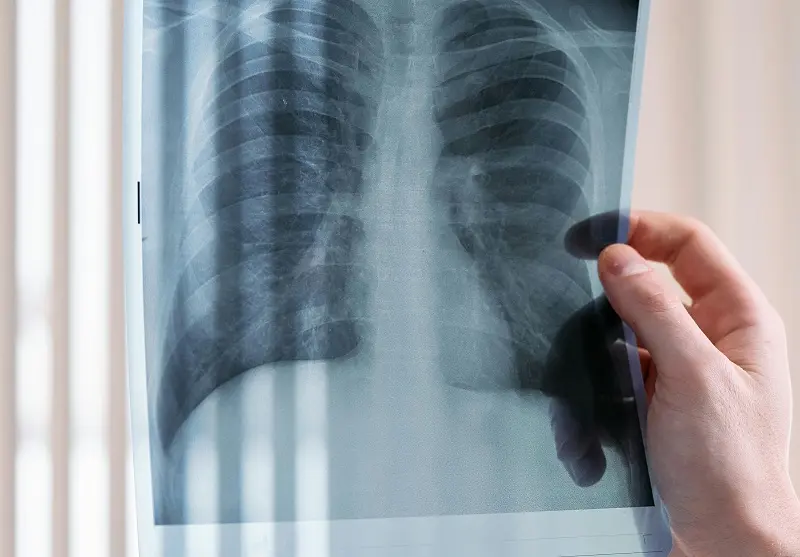

Un equipo médico chino ha logrado lo que hasta hace poco parecía ciencia ficción: realizar con éxito el primer trasplante de pulmón de un cerdo a un ser humano. (Imagen superior de cottonbro studio en Pexels).